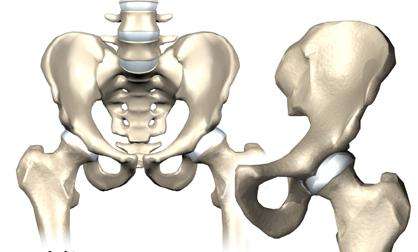

先天性髋关节脱位是小儿比较常见的先天性畸形之一,以后脱位为多见,出生时即已存在,病变累及髋臼、肌骨头、关节囊、韧带和附近的肌肉,导致关节松弛,半脱位或脱位。有时可合并有其它畸形,如先天性斜颈、脑积水、脑脊膜膨出,其它关节先天性脱位或挛缩等。

2、在儿童时期先天性髋关节脱位的危害,患儿会出现先天性斜颈、脑积水、脑脊膜膨出、其它关节先天性脱位或挛缩等疾病。部分患儿的脱位可在一定时期内自愈,若自愈后位置欠缺,会造成髋关节疼痛,形成扁平髋,甚至影响到股骨头附近的血运还可能导致股骨头坏死。